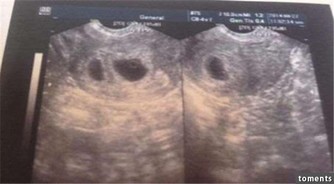

8、懷孕時促進血液循環

最適合孕媽咪的睡姿是採取左側睡,因為右側睡容易導致下腔靜脈遭受壓迫,造成血液循環不良,左側睡就不會壓迫到下腔靜脈血液回流系統,血液循環順暢後,相對供應給胎兒的養分就可以更多。